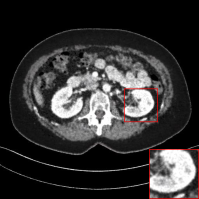

Figure 4: Qualitative results of our method and other baselines on Mayo Clinic Low Dose CT dataset. (a) Real low-dose. (b)-(f) Results of each methods. (g) Real normal-dose. As shown in the highlighted red box, the reconstructed image by our method has few noise and artifacts. The display window is [160,240]160240[160,240] HU.

PSNR (dB) 29.16 29.39 26.97 27.26 30.11

SSIM 0.8514 0.9078 0.8267 0.8452 0.8728

Table 2: The average PSNR and SSIM results of different methods on Mayo Clinic Low Dose CT dataset. Our results are marked in bold.

Denoising on Low-Dose CT

Since Computed Tomography (CT) helps to diagnose abnormalities of organs, CT is widely used in medical analysis. Reducing the radiation dose in order to decrease health risks causes noise and artifacts in the reconstructed images. Like the real-world noise, the noise distributions of the reconstructed image are difficult to model analytically. Therefore, we adopt a CT dataset authorized by Mayo Clinic [Moen etย al.(2021)Moen, Chen, Holmesย III, Duan, Yu, Yu, Leng, Fletcher, and McCollough] to evaluate the generalization ability of our method on real-world noise. Mayo Clinic dataset consists of paired normal-dose and lose-dose CT images for each patient. The Normal-Dose CT (NDCT) and the Low-Dose CT (LDCT) images correspond to clean and noisy images, respectively. For the training, we obtain 2,850 images in 512ร—512512512512\times 512 resolution from 20 different patients. We construct 1,422 LDCT images from randomly selected 10 patients as a noise set and 1,428 NDCT images from the remaining patients as a clean set for unpaired training. For the test, we obtain 865 images from 5 different patients. As shown in Table 2, our method achieves the best and the second-best performance in PSNR and SSIM, respectively. Note that our model trained on the unpaired dataset outperforms the RED-CNN trained on the paired dataset in PSNR. It indicates that our method can be more practical in medical analysis where obtaining paired datasets is challenging. We also compare the qualitative results with other baselines. As shown in Figure 4, other methods tend to generate artifacts or lose details. On the other hand, our method shows a reasonable balance between noise removal and image quality. More qualitative results are provided in the supplementary material.